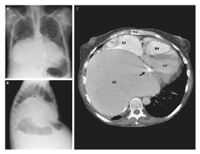

1例59岁的风湿性心脏病妇女因腹水增加8个月而就诊。病人由于二尖瓣狭窄已于20年前接受了Bjork-Shikey二尖瓣置换术。胸部X线显示心脏扩大(图A和B)。胸部CT扫描显示左心房(LA)重度扩大(图C),15.0 cm×15.8 cm,充满全部右下胸腔,压迫左心室(LV)、右心室(RV)和右心房向前胸壁。Bjork-Shikey瓣膜前移(箭头)。超声心动图显示,室间隔的舒张突然停止,血液动力学描记呈Y型快速下降——与狭窄的生理学过程一致。 病人接受连续的腹水穿刺术和积极地用利尿剂。但病人在入院后不久即死于新诊断的急性粒细胞性白血病。由于全心炎症伴偏心扩张,巨大左心房几乎是类风湿性心脏病病人特有的体征。